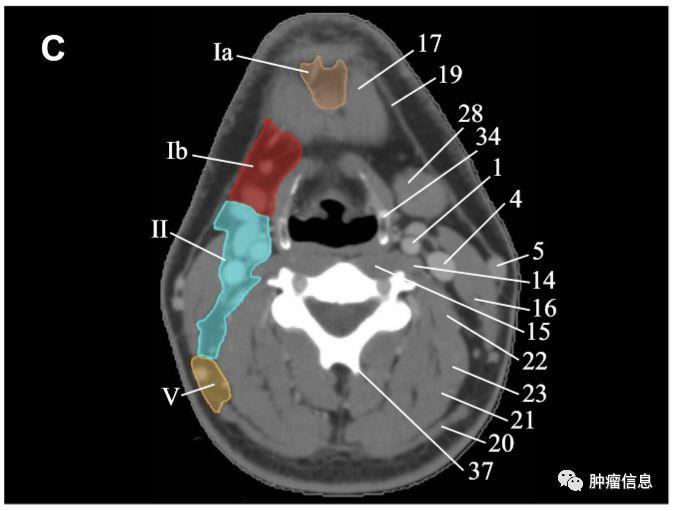

颈部I区淋巴结

上界:下颌舌骨肌下界:舌骨前界:下颌骨前缘后界:颌下腺后缘内侧界:二腹肌前腹外缘外侧界:下颌骨内侧缘IA:颏下淋巴结(前正中线至二腹肌前腹与舌骨下缘之间的区域)IB:颌下淋巴结(下颌骨上缘,二腹肌前腹与颌下腺后缘之间的区域)

颈部I区图中淡黄色为Ia图中红色为Ib

颈部II区淋巴结

上界:颅底下界:舌骨上缘前界:颌下腺后缘后界:胸锁乳突肌后缘内界:颈血管鞘内缘外侧界:胸锁乳突肌内缘IIA:颈动脉前区IIB:颈动脉后区

颈部II区图中绿色为II区

颈部V区淋巴结

上界:颅底下界:锁骨上缘前界:胸锁乳突肌后缘后界:斜方肌前缘VA:环状软骨下缘以上区域VB:环状软骨下缘至锁骨上缘区域

颈部V区图中黄色为V区

RTOG2013年头颈部淋巴结分区勾画图谱:

Ia:颏下淋巴组Ib:颌下淋巴组II:上颈淋巴组III :中颈淋巴组IVa:下颈淋巴组IVb:锁骨上内侧组V:颈后三角淋巴组Va:上颈后三角淋巴组Vb:下颈后三角淋巴组Vc:锁骨上外侧组VI:颈前淋巴组VIa:颈前淋巴结VIb:喉前、气管前、气管旁淋巴结VII:椎前淋巴组VIIa:咽后淋巴结VIIb:茎突后淋巴结VIII:腮腺淋巴组IX:面颊淋巴组X:颅底后组Xa:耳后、耳下淋巴结Xb:枕淋巴结见下图: